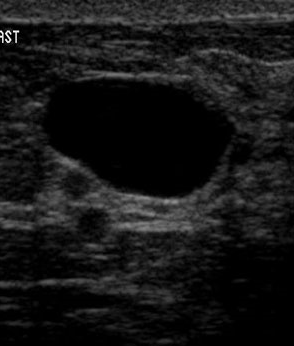

The target dataset was developed from 35 breast ultrasound scans that were segmented by an image-processing expert with extensive experience in breast lesion segmentation (the second author). The images, collected from the Web, are of different dimensions, ranging from to pixels (Figure 3, images resized for sake of illustration). These are the same images used to introduce EFIS originally [1].

Ultrasound images are generally difficult to segment, primarily due to the presence of speckle noise and low level of local contrast. It should be noted that the segmentation of ultrasound actually does require a complete processing chain, (including proper preprocessing and post-processing steps). However, the purpose of using these images was solely to demonstrate that the accuracy of the segmentation can be increased with the application of SC-EFIS.